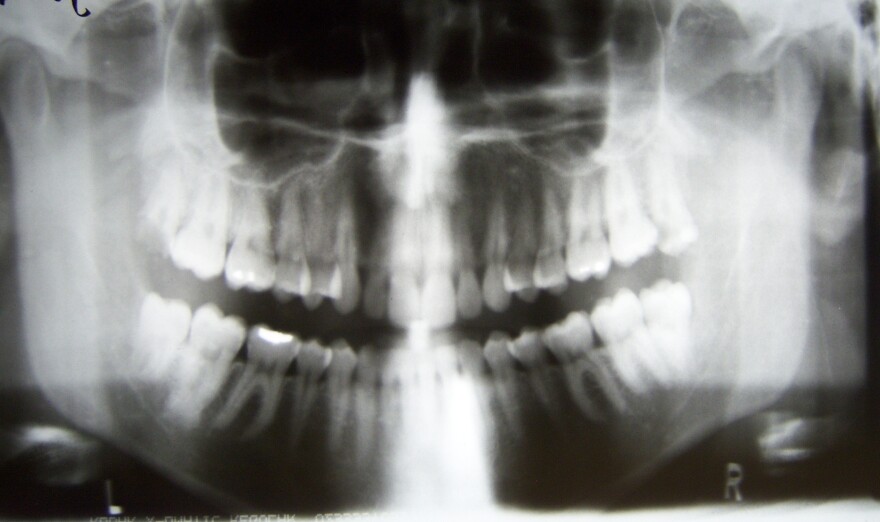

A dental X-ray.

Dental X-rays produce ionizing radiation, which has been linked to non-cancerous brain tumors called meningiomas. Although they’re benign, the tumors can cause seizures, blindness and even, if left untreated, death.

The researchers examined the dental histories of the participants, including those who had the higher-radiation X-rays of the past. The study did not focus on the effect of new lower-radiation methods.

Researchers found that patients with tumors were twice as likely to have had the older technology X-rays. People who had routine X-rays every year before the age of 10 were nearly five times as likely to develop the meningiomas.

The study compared nearly 1,500 people diagnosed with brain tumors and a control group of nearly the same size.

Older studies looked at people exposed to high levels of this radiation from atomic bombs or cancer treatments. This new study, led by Yale researchers, is the first to focus on dental X-rays even though they're acknowledged to be the most common type of exposure.

The study was published in the April 10 issue of the American Cancer Association journal Cancer and was funded in part by the National Institutes of Health.